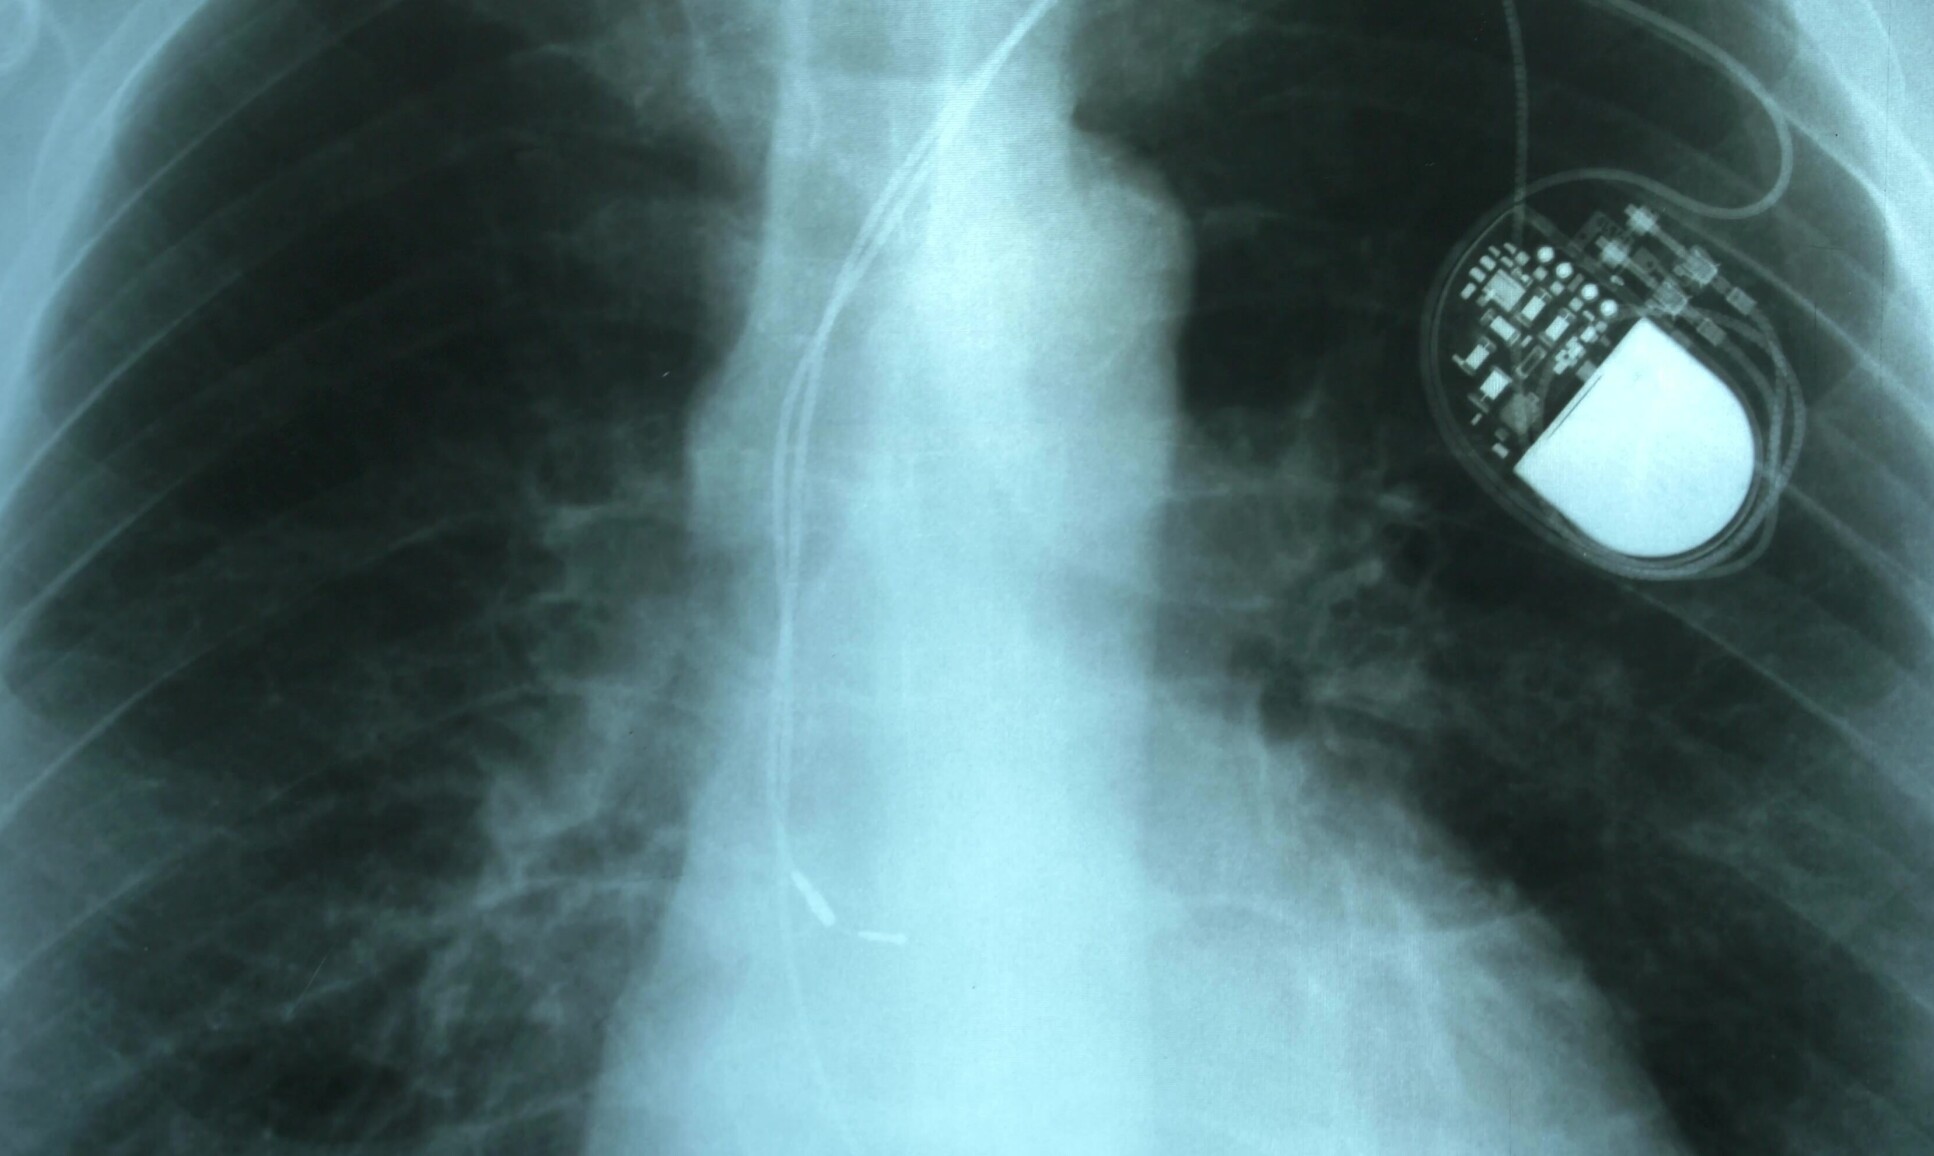

pacemaker

Academics from Imperial and NTU Singapore are developing better ways to protect implantable active devices, such as pacemakers.

Academics from Imperial and NTU Singapore have been awarded a four-year S$20million grant from NRF Singapore to develop better ways to protect implantable active devices, such as pacemakers, and secure the data protection of connected wearables and healthcare systems.

As technology in healthcare improves and more personal data are collected and stored, there have been security concerns about the risks and threats of personal data being stolen or medical devices operation being disrupted by accidental or malicious actors.

Imperial’s Professor Anil Anthony Bharath and NTU Singapore’s Professor Liu Yang will lead the research programme, called IN-CYPHER, which brings together complementary expertise from Imperial and NTU Singapore to tackle existing security challenges, and to protect emerging sensing technologies – and their data – from being compromised. The team believe that the research will have applications for a range of devices such as continuous glucose monitors, smart electronic skin patches and activity monitors.